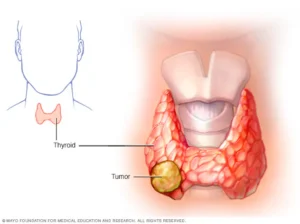

استئصال الغدة الدرقية هو إزالة الغدة الدرقية بالكامل أو جزء منها جراحيًا. والغدة الدرقية هي غدة على شكل فراشة، توجد في الرقبة من الأمام. وهي

ورم الغدة الجار درقية (بالإنجليزية: Parathyroid Tumor) هو نمو داخل 1 من 4 غدد جارات الدرقية في الجسم. تقع هذه الغدد في الرقبة أو أعلى

سرطان الغدة الدرقية الأسباب، الأعراض، والأنواع – دليل شامل من دكتور عمرو نوفل يُعد سرطان الغدة الدرقية من أنواع السرطان التي تبدأ في خلايا الغدة